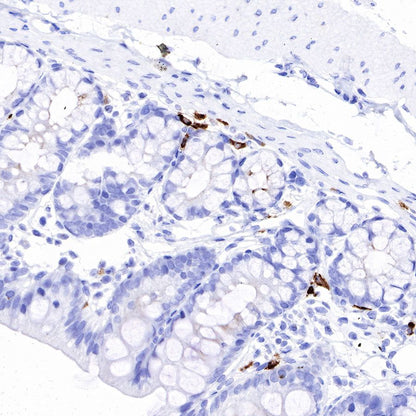

IHC shows positive staining in paraffin-embedded rat colon. Anti-IGJ antibody was used at 1/1600 dilution, followed by a HRP Polymer for Mouse & Rabbit IgG (ready to use). Counterstained with hematoxylin. Heat mediated antigen retrieval with Tris/EDTA buffer pH9.0 was performed before commencing with IHC staining protocol.